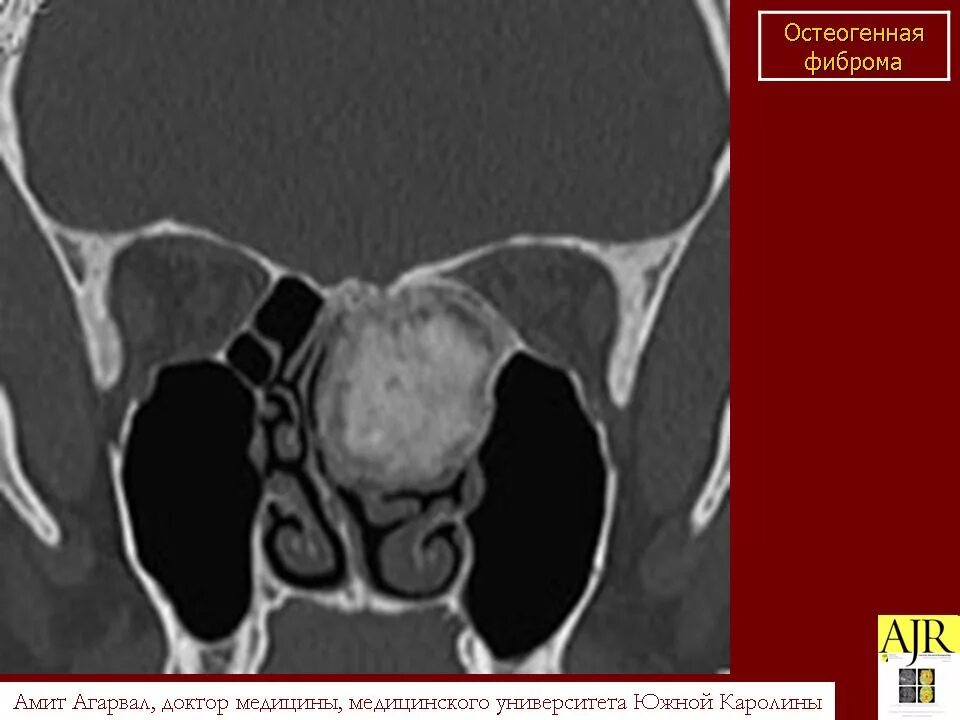

Фиброма кт